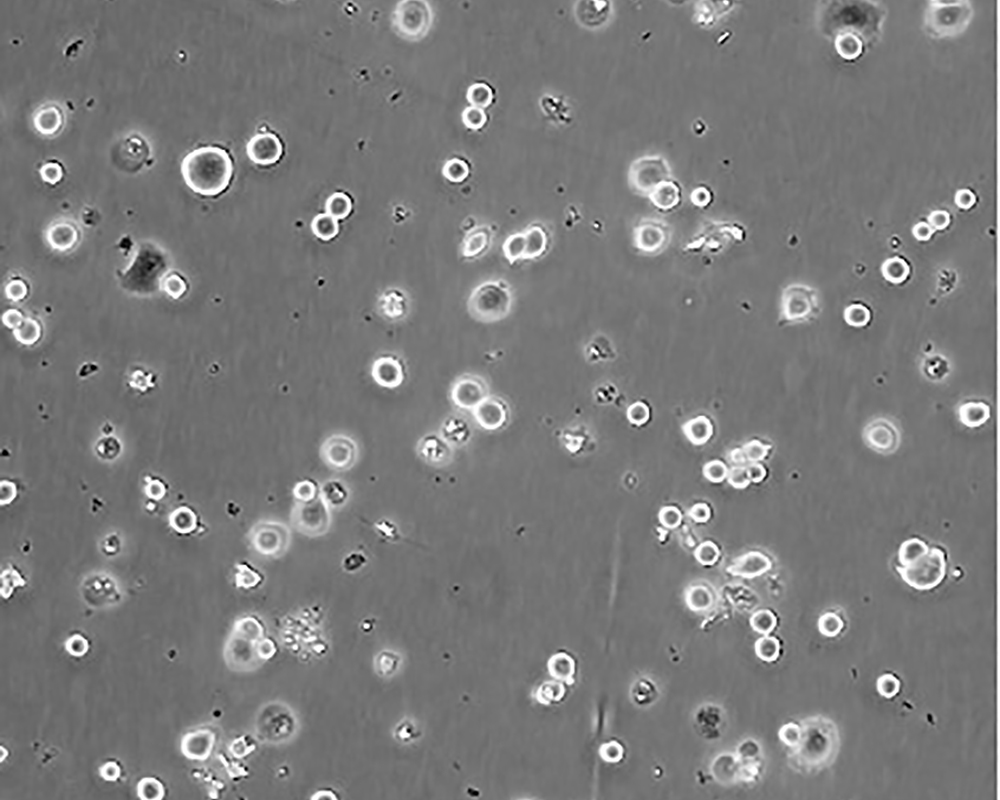

SK-BR-3 [SKBR-3;SKBR3]

產品名稱 SK-BR-3 [SKBR-3;SKBR3]

中文名稱 人乳腺腺癌細胞

組織來源 mammary gland/breast; derived from metastatic site: pleural effusion

生長特性 adherent

形態特征 epithelial

細胞描述 he patient, a White, Caucasian female, age 43, blood type A+, had been treated with radiation, steroids, cytoxan and 5-fluorouracil.No virus particles.Ultrastructural features include microvilli and desmosomes, glycogen granules, large lysosomes, bundles of cytoplasmic fibrils.The SKBR- 3 cell line overexpresses the HER2/c-erb-2 gene product.